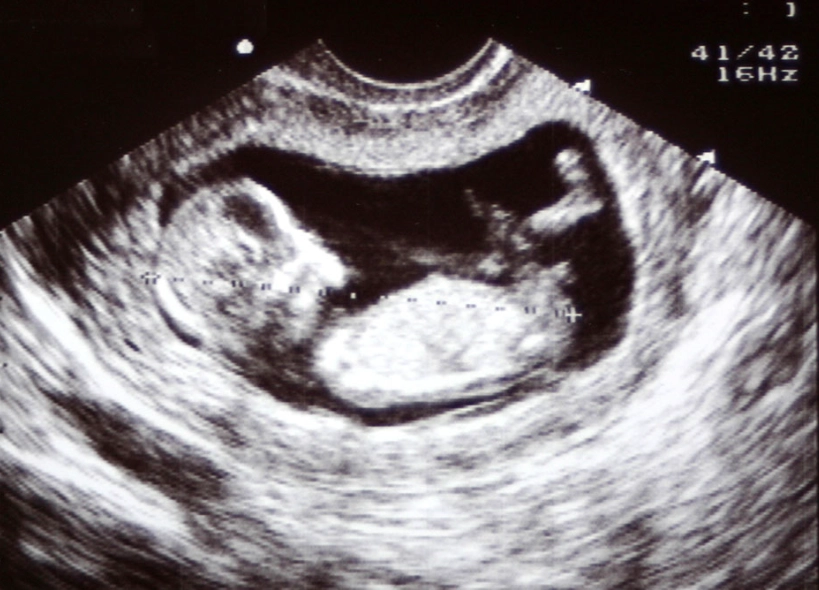

Forget the month debate. The 12-week scan is where the magic—and the medicine—happens. This is often the first detailed look at your baby, and the emotional impact is huge. It's not just a blurry blob anymore.

The "Wow" Factor: What You'll Actually See

While the tech is taking measurements, you'll get to watch. At 12 weeks, your baby looks undeniably human.

| Arms and legs with tiny hands and feet | Your baby is moving, maybe even waving or kicking, though you might not feel it yet. |

| A flickering heartbeat | The heart is fully formed and beating between 120-160 beats per minute. They'll measure this. |

| The nasal bone | The presence of a visible nasal bone is another soft marker screened for. |

| The stomach and bladder | They're starting to function! The baby swallows amniotic fluid. |

You might also get confirmation if you're having twins (or more!). This scan checks for separate amniotic sacs and placentas, which is vital information for your care.